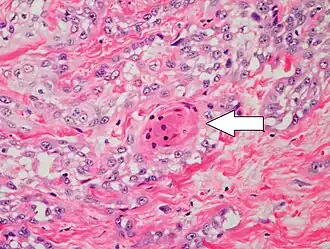

Degree of differentiation

![Well-differentiated (yet invasive) cSCC, showing prominent keratinization. It may form pearl-like structures where dermal nests of keratinocytes attempt to mature in a layered fashion. Well-differentiated cSCC has slightly enlarged hyperchromatic nuclei with abundant amounts of cytoplasm. Intercellular bridges will frequently be visible.[12]](./Micrograph_of_well-differentiated_and_invasive_squamous-cell_carcinoma.jpg) Well-differentiated (yet invasive) cSCC, showing prominent keratinization. It may form pearl-like structures where dermal nests of keratinocytes attempt to mature in a layered fashion. Well-differentiated cSCC has slightly enlarged hyperchromatic nuclei with abundant amounts of cytoplasm. Intercellular bridges will frequently be visible.[12]

Well-differentiated (yet invasive) cSCC, showing prominent keratinization. It may form pearl-like structures where dermal nests of keratinocytes attempt to mature in a layered fashion. Well-differentiated cSCC has slightly enlarged hyperchromatic nuclei with abundant amounts of cytoplasm. Intercellular bridges will frequently be visible.[12] -

Poorly differentiated clear-cell squamous-cell carcinoma. For this type of cSCC, immunostains will likely be required to classify it unless other areas of the tumor show obvious squamous-cell features, such as seen here (arrow).

Poorly differentiated clear-cell squamous-cell carcinoma. For this type of cSCC, immunostains will likely be required to classify it unless other areas of the tumor show obvious squamous-cell features, such as seen here (arrow).